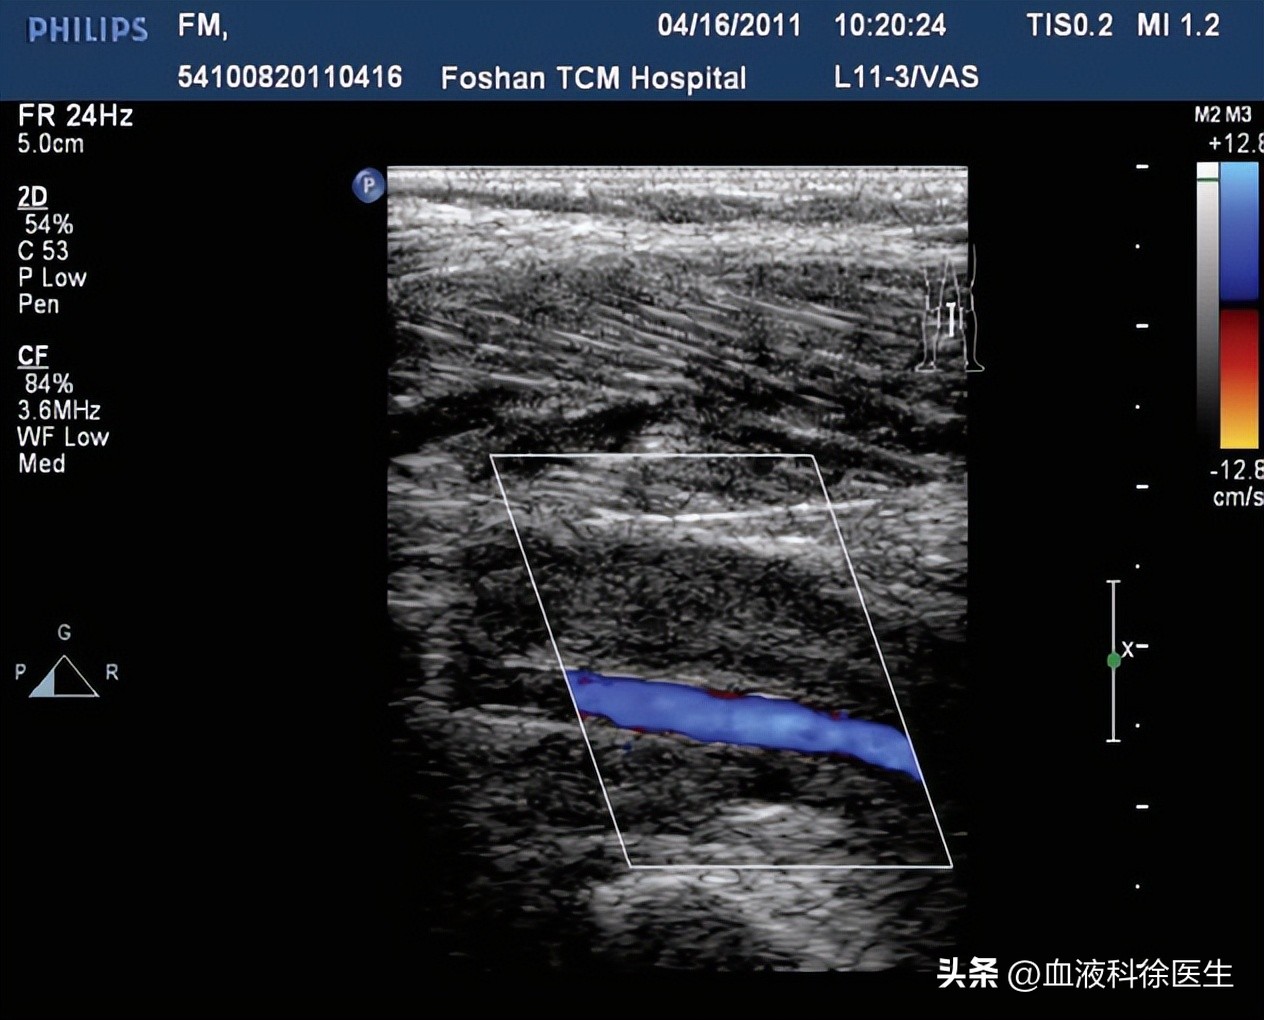

医生怀疑张先生是骨折后并发下肢深静脉血栓形成,安排血管B超检查。血管B超显示:左髂外至胫后静脉中上段血栓形成,完全阻塞,左小腿肌内静脉血栓形成。于是医院立即对张先生进行了抗凝、溶栓等治疗。经过治疗,张先生的肌无力和疼痛麻木都消失了。